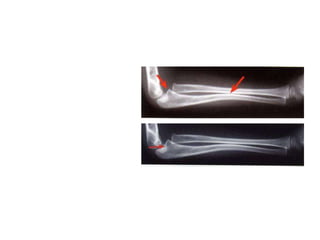

• Intramedullary wires, elastic nails

– Very useful

– Diaphyseal fractures